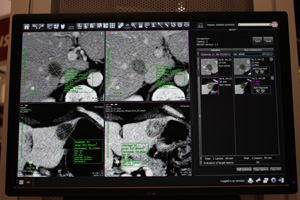

●逐次近似画像再構成応用技術「iIR」(W.I.P.)

iIR(image-based Iterative Reconstruction)は,従来はCT本体でしか実行することができなかった逐次近似再構成を,ワークステーション側で応用する技術である。CTからワークステーションに取り込んだ画像データを順投影によりサイノグラムデータに戻し,その投影データに逐次近似画像再構成を応用して画像を再構成し直すという方法で,ノイズの少ない画像をポストプロセスで取得することができる。撮影画像のノイズを低減できるようになるため,撮影時の被ばく線量低減に貢献する。まずは被ばく線量が多いとされるCT Perfusionへの適応から開発が進められている。

逐次近似画像再構成が搭載されていないCTの画像に対して実行できるだけでなく,逐次近似画像再構成による画像に対しても同様の方法で実行することができるため,さらなるノイズ低減を図ることが期待される。iIRにより,逐次近似画像再構成が搭載されていないCT装置を使用している中小規模の病院やクリニック,低被ばく検査が求められる検診施設などでの利用が想定される。

iIRは,VirtualPlaceに搭載するソフトウェアとして提供するとともに,CTメーカーへのOEM供給も検討しているという。来春のITEM 2014での詳細な発表をめざして開発が進められている。